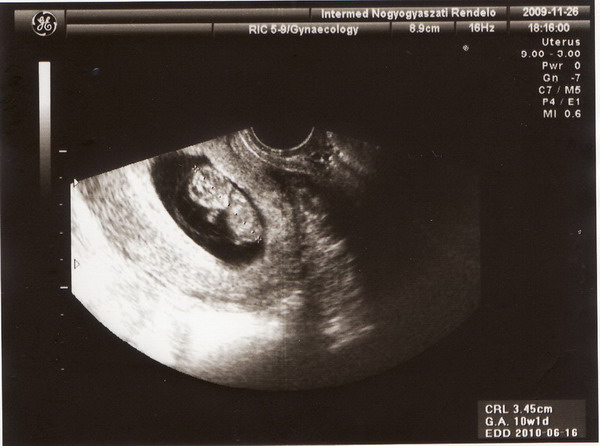

6+6hetes8mm

6+6hetes8mm 10+1hetes34mm

10+1hetes34mm